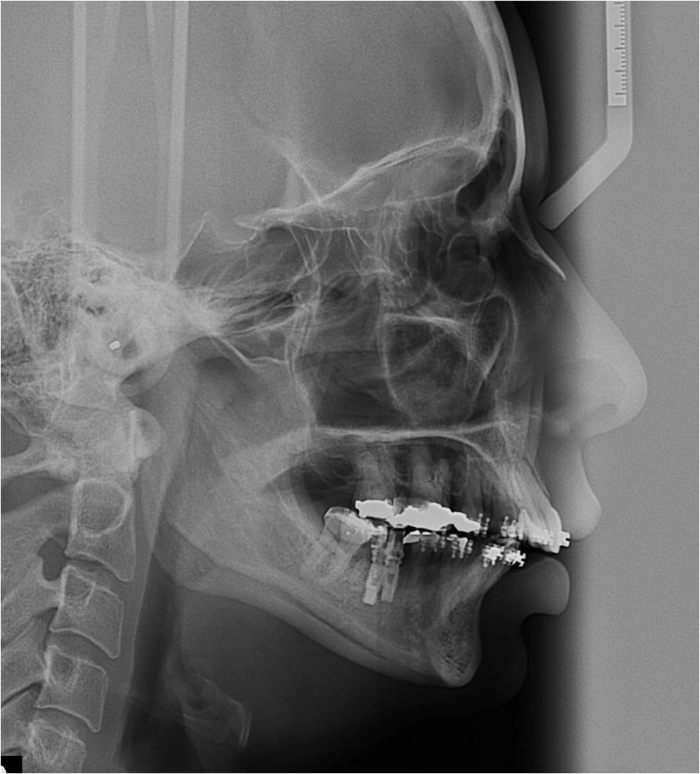

Raio x inicial

Telerradiografia inicial